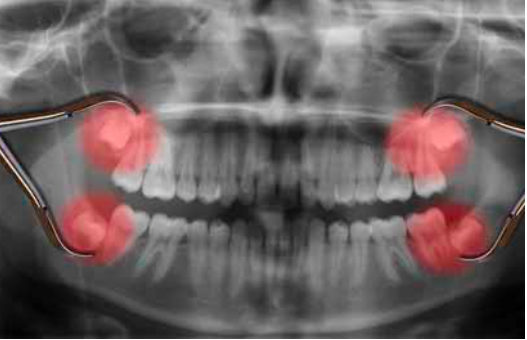

расположение зубов мудрости